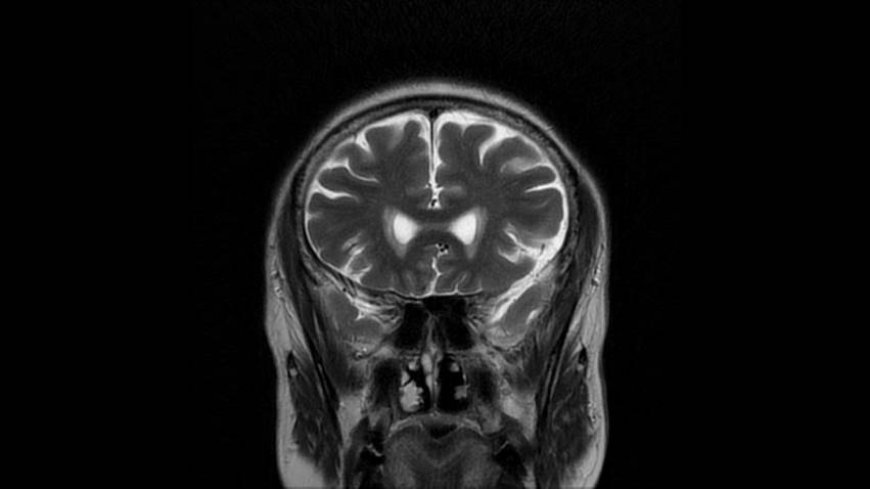

MRI of Brain

Coronal T2